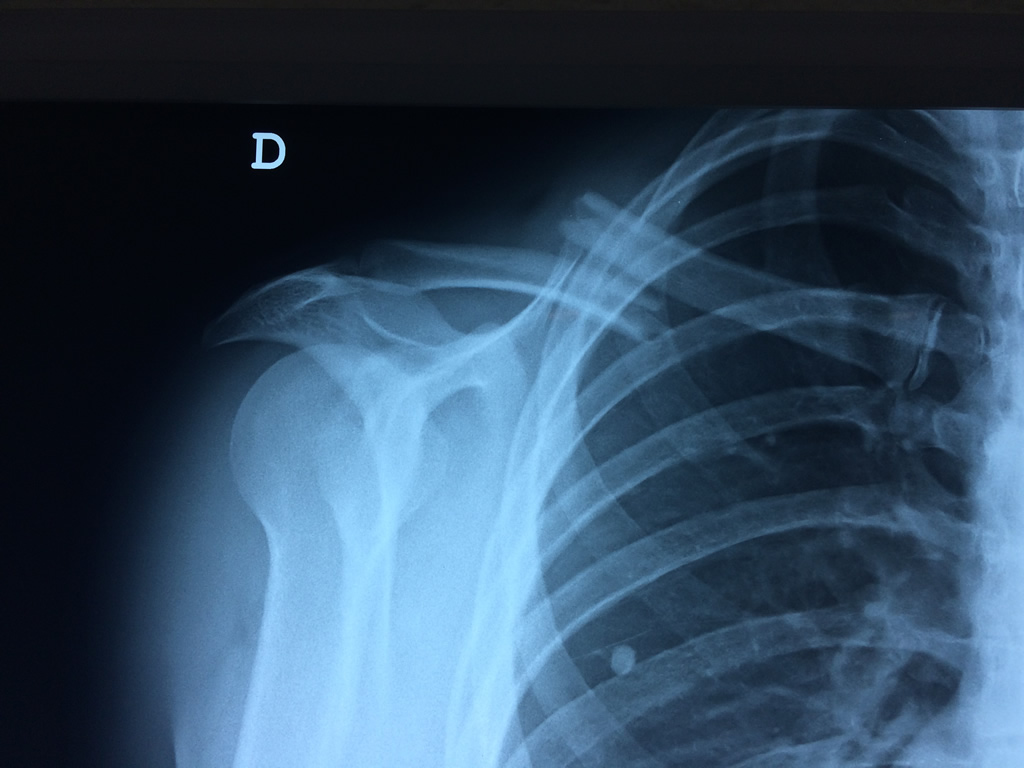

Cirugías de Codo - Clavícula

La clavícula es un hueso largo, con forma de "S" itálica, situado en la parte anterosuperior del tórax. Junto con la escápula forman la cintura escapular. Se puede palpar por toda su longitud y se extiende del esternón al acromion de la escápula, siguiendo una dirección oblicua lateral y posterior.